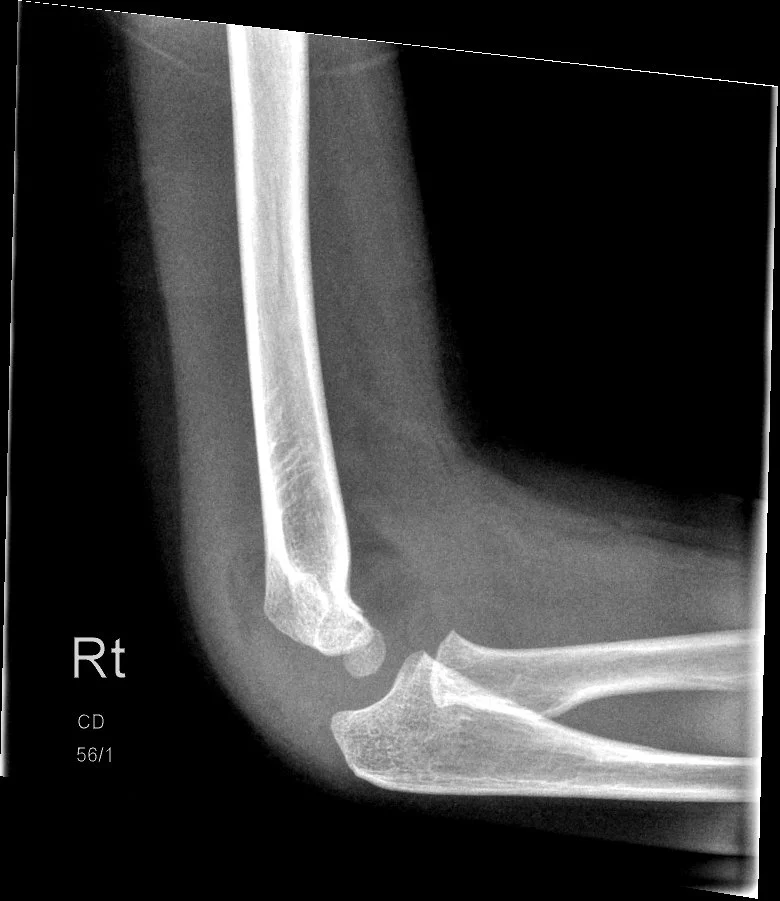

SCH-RCT

This is a study revolving around upper arm fractures which aims to compare a new removable cast treatment to a traditional cast. We wish to prove that the removable cast offers equal immobilization and healing while having the added benefit of at-home removal.

Automated Identification and management guidance of pediatric elbow fractures